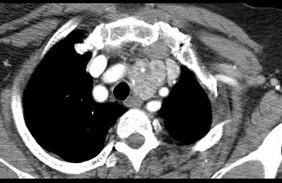

问题 40岁,女,发现颈部肿块,随吞咽上下移动,触之无搏动,咳嗽、气喘一周,请结合CT图。检查选择最可能的诊断 ( )

选项 A、无名动脉伸展扭曲 B、淋巴瘤 C、胸内甲状腺瘤 D、无名动脉瘤 E、胸腺瘤

答案 C